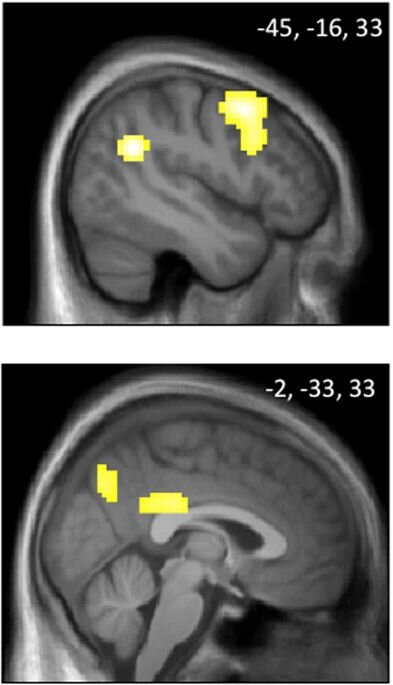

-2

Распределение ресурсов шло по очереди каждым игроком. Начиная со второго раунда человек мог мстить нехорошему боту. Часть испытуемых до конца игры были максимально честными, другие мстили. При проявлении мщении учёные фиксировали возбуждении в амигдале и верхней височной доли мозга. А если игрок действовал сдержано, то была более низкая активность этих зон. Соответственно, воздействую определённым образом на них, можно будет контролировать жажду мести.

Испытуемые делали ставки, а компьютер сообщал о выигрыше или проигрыше. При поражении игрок испытывал сожалению, и активизировалась определённая зона в орбитофронтальной коре. Но затем учёные поняли, что игроки испытывали сожаление постоянно. При проигрыше жалели, что поставили не на то, а при победе, что поставили мало.

-4

Руководитель работ Роберт Найт вспомнил американского железнодорожника Финеаса Гейджа. Ему пробило мозг железным стержнем в орбитофронтальной области. Он выжил, но изменился, стал действовать без сожаления, «без тормозов». Очевидно, повреждённая область отвечает за сожаление или совесть. Соответственно, манипуляция с этой областью позволит усилить или ослабить эти чувства.